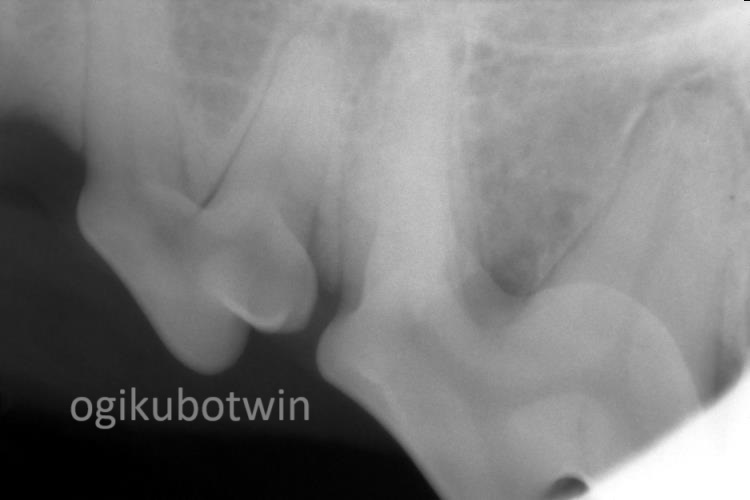

まず、全身麻酔下にて歯科レントゲンを撮影し、歯石除去を行いました。

第四前臼歯は右側の方が歯周病は進行しており、歯肉でフラップを形成し、エムドゲインを注入し再生治療を行いました。